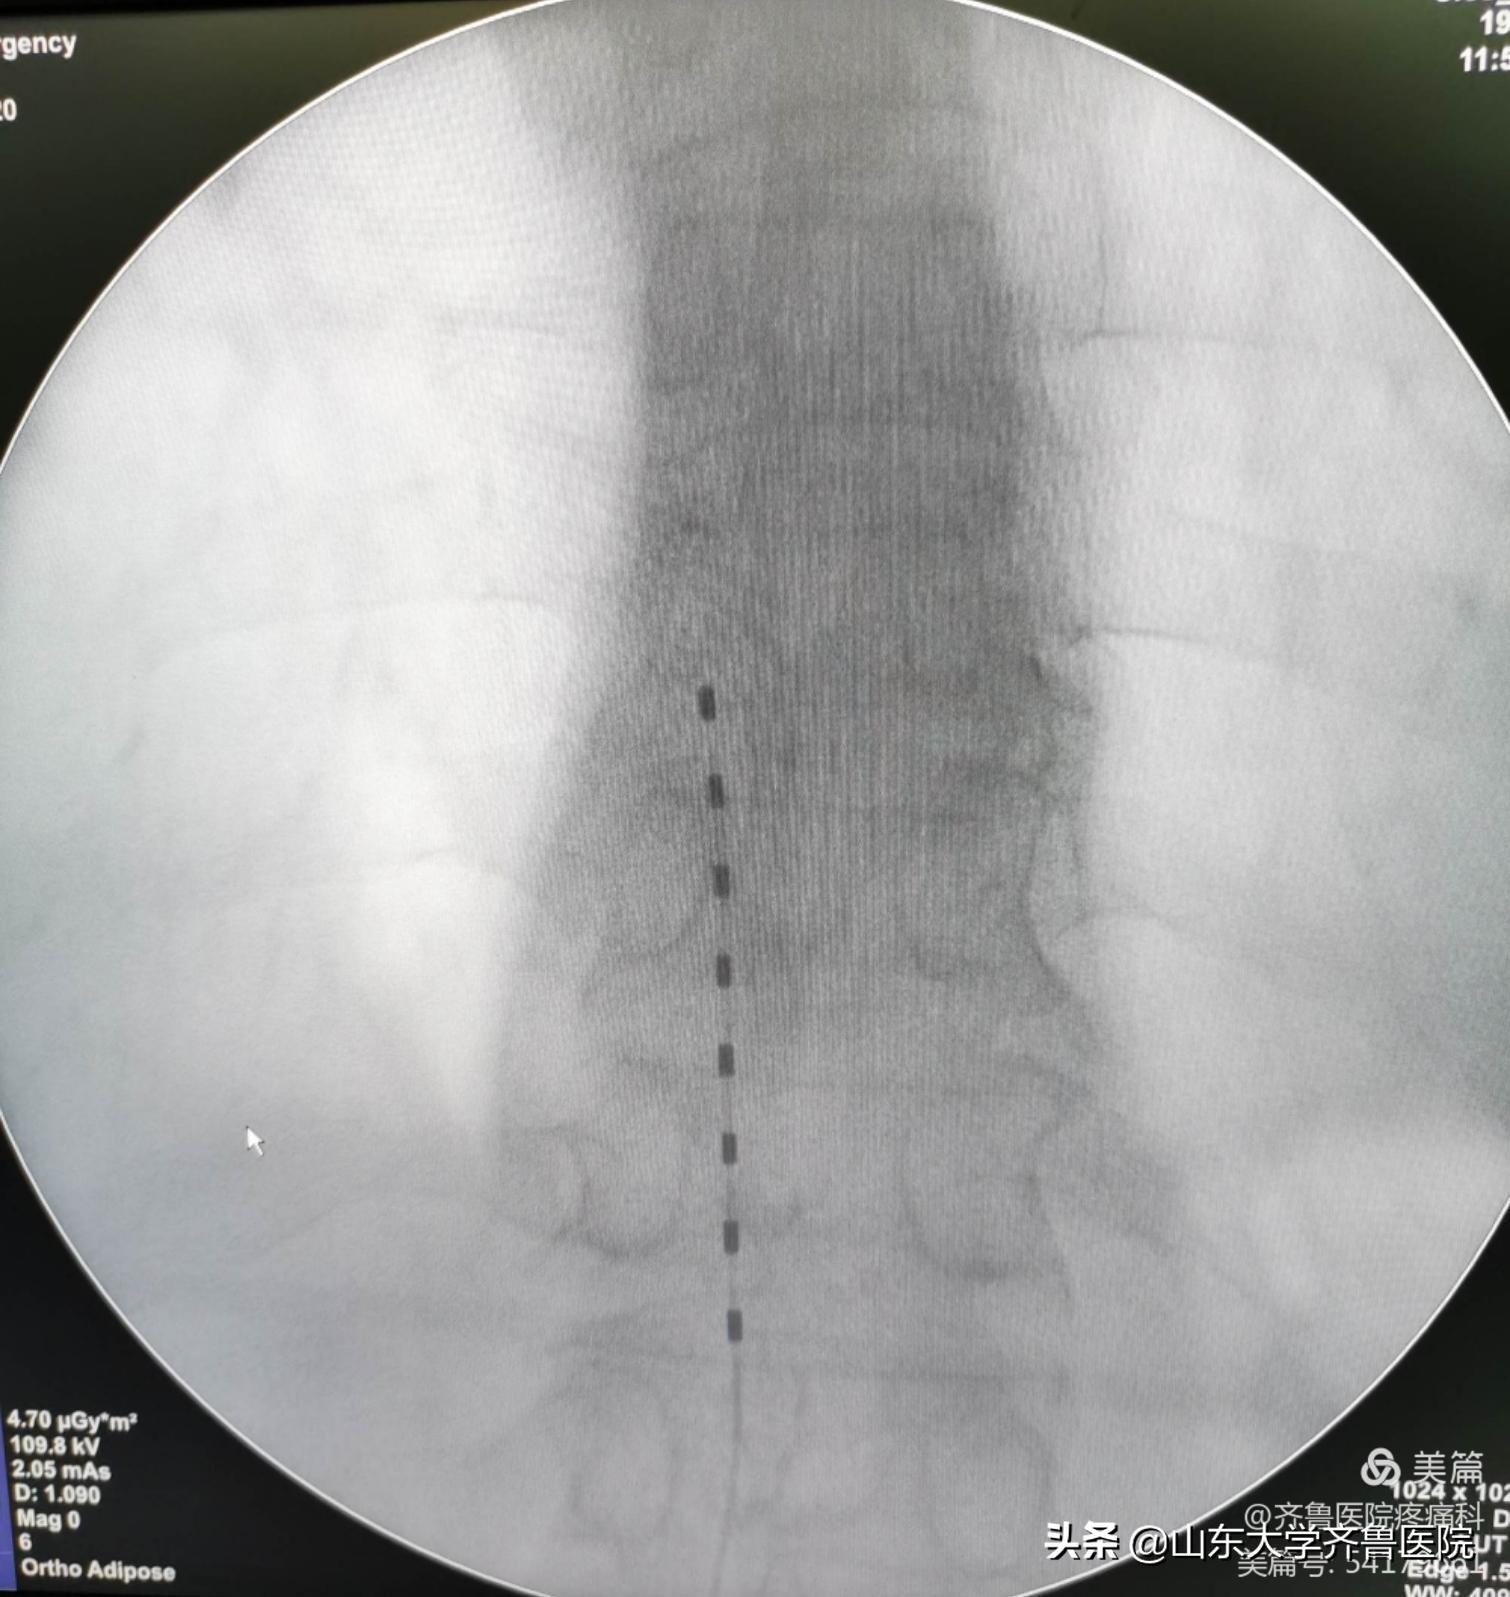

图1.带状疱疹性神经痛患者术后X线检查电极位置良好